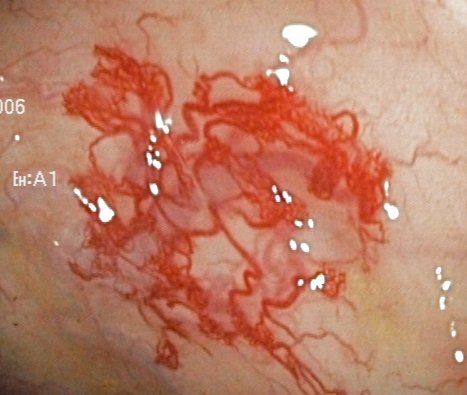

Hochauflösende Video-Endoskope und der Einsatz von speziellen Techniken (Chromoendoskopie, Bildverarbeitung) ermöglichen das Auffinden auch kleinster verdächtiger Veränderungen im gesamten Dickdarm und den unteren Anteilen des Dünndarms.